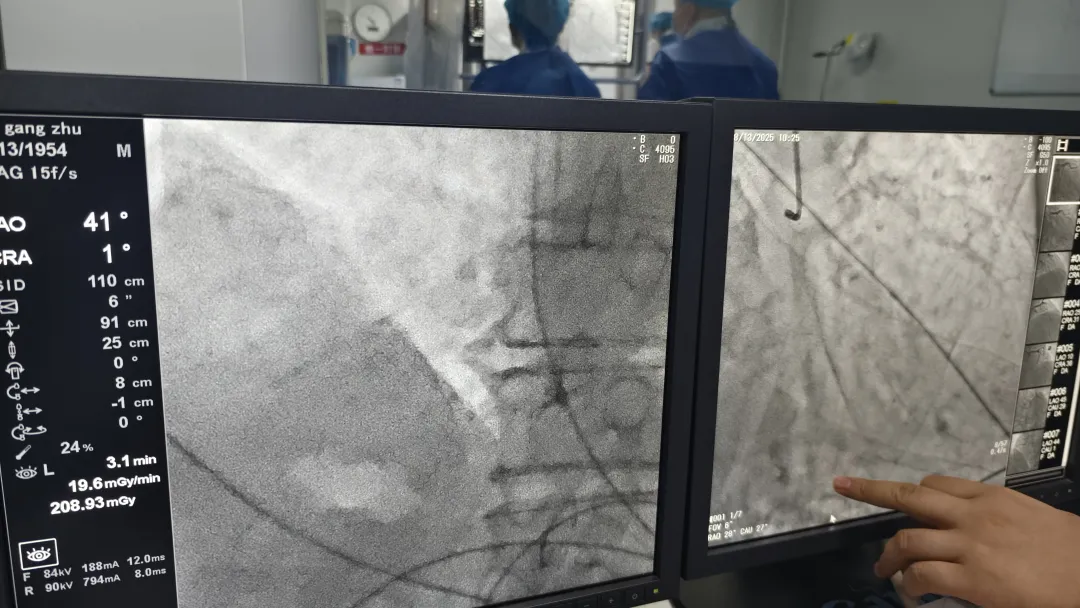

8月13日,駐馬店廣濟(jì)心血管病醫(yī)院暨武漢亞洲心臟病醫(yī)院豫南醫(yī)院心臟中心和神經(jīng)外科介入團(tuán)隊(duì)成功完成了院內(nèi)首例心血管和腦血管聯(lián)合造影術(shù)。一臺(tái)手術(shù),一次解決患者兩個(gè)難題,這一舉措不僅標(biāo)志著我院在心腦血管疾病診療水平在此邁上新臺(tái)階,也為患者帶來(lái)了更為高效、便捷的醫(yī)療服務(wù)體驗(yàn)。

一切準(zhǔn)備就緒,在局麻下,神經(jīng)外科介入團(tuán)隊(duì)經(jīng)過(guò)患者右側(cè)橈動(dòng)脈顱內(nèi)血管造影術(shù),術(shù)中造影清晰顯示:李大爺腦血管存在一處60%的狹窄。隨后,心臟中心吳少威主任和董鶴翔主任經(jīng)過(guò)同樣的路徑進(jìn)行冠脈造影術(shù),結(jié)果顯示,前降支和回旋支血管均存在重度狹窄病變。這些關(guān)鍵發(fā)現(xiàn)為后續(xù)制定精準(zhǔn)的治療策略提供了強(qiáng)有力的影像學(xué)依據(jù)。